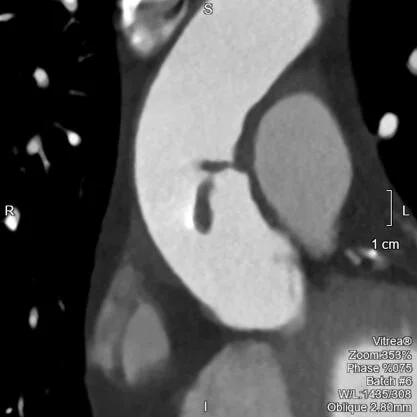

Odd linear filling defect in aorta

The filling defect is confirmed on 40 keV image.

Gated CTA shows filling defect is mobile. Video on my twitter feed (@CtSpectral).